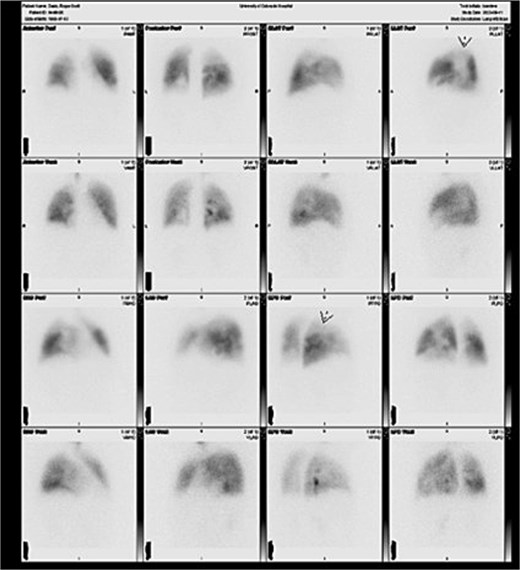

Informed written consent was obtained. A 68-year-old male with history of CTEPH, chronic obstructive pulmonary disease, coronary artery disease, chronic osteomyelitis, Type II diabetes, and persistent atrial fibrillation presented with worsening dyspnea requiring home oxygen. Preoperative evaluation showed mean pulmonary artery pressure 42 mmHg, PCWP 11 mmHg, PVR 8.66 Wood units, and bilateral mismatches on ventilation–perfusion (V/Q) scan (Fig. 1). Coronary angiogram revealed multivessel disease. Echocardiogram showed severe eccentric aortic insufficiency, ascending aortic aneurysm, PFO, and enlarged right ventricle (RVSP 77 mmHg). Multidisciplinary review deemed the patient suitable for PTE with concomitant procedures.

Preoperative ventilation-perfusion (V/Q) scan demonstrating bilateral segmental and subsegmental perfusion defects consistent with chronic thromboembolic pulmonary hypertension.